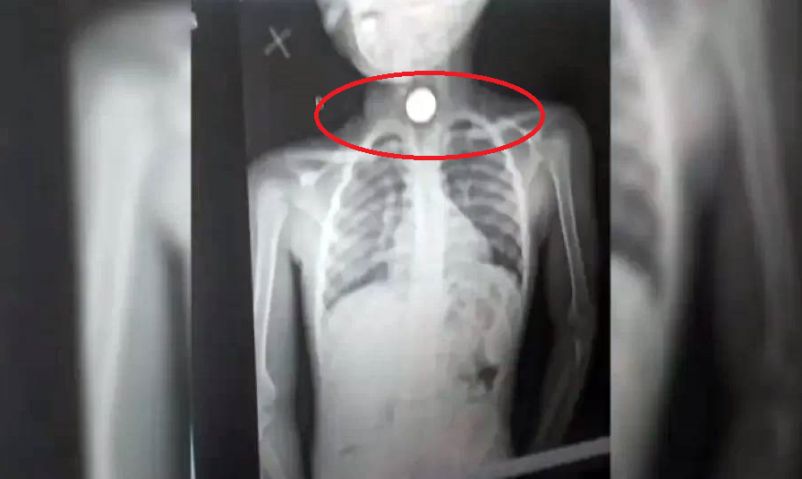

Os casos de ingestão de corpo estranho têm vindo a crescer no Hospital Pediátrico David Bernardino.

Dados do hospital indicam que, de Dezembro do ano passado à presente data, foram atendidos mais de 120 casos em crianças com idades compreendidas entre os três meses e os cinco anos.

Os números preocupam a direcção do hospital, que apela aos pais e encarregados de educação a reforçarem a vigilância. Jornalista Patrícia Van-Dúnem Campos. Clique no áudio e ouça: